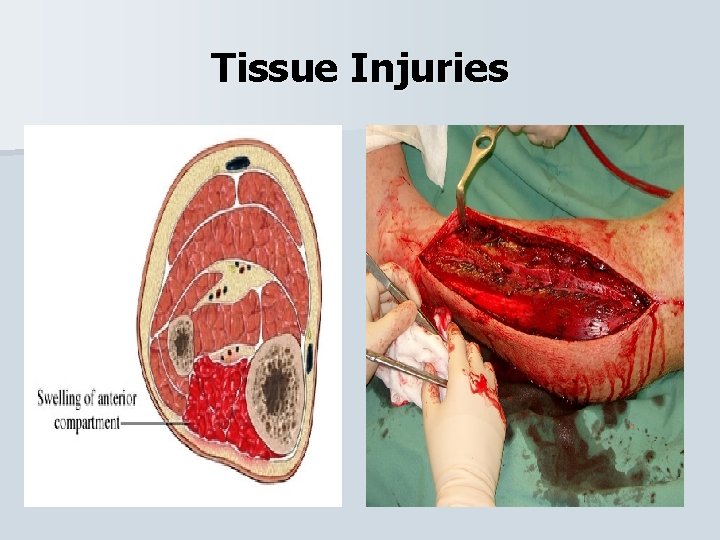

Tissue Injuries Anterior Compartment Syndrome Sometimes mistaken for shin splints, this injury involves the muscles anterior to the tibia that are enclosed in connective tissue. An impact or overuse can cause pressure (swelling) within the compartment and severe pain. The athlete will experience heat, red skin, loss of function and hardness in the area.